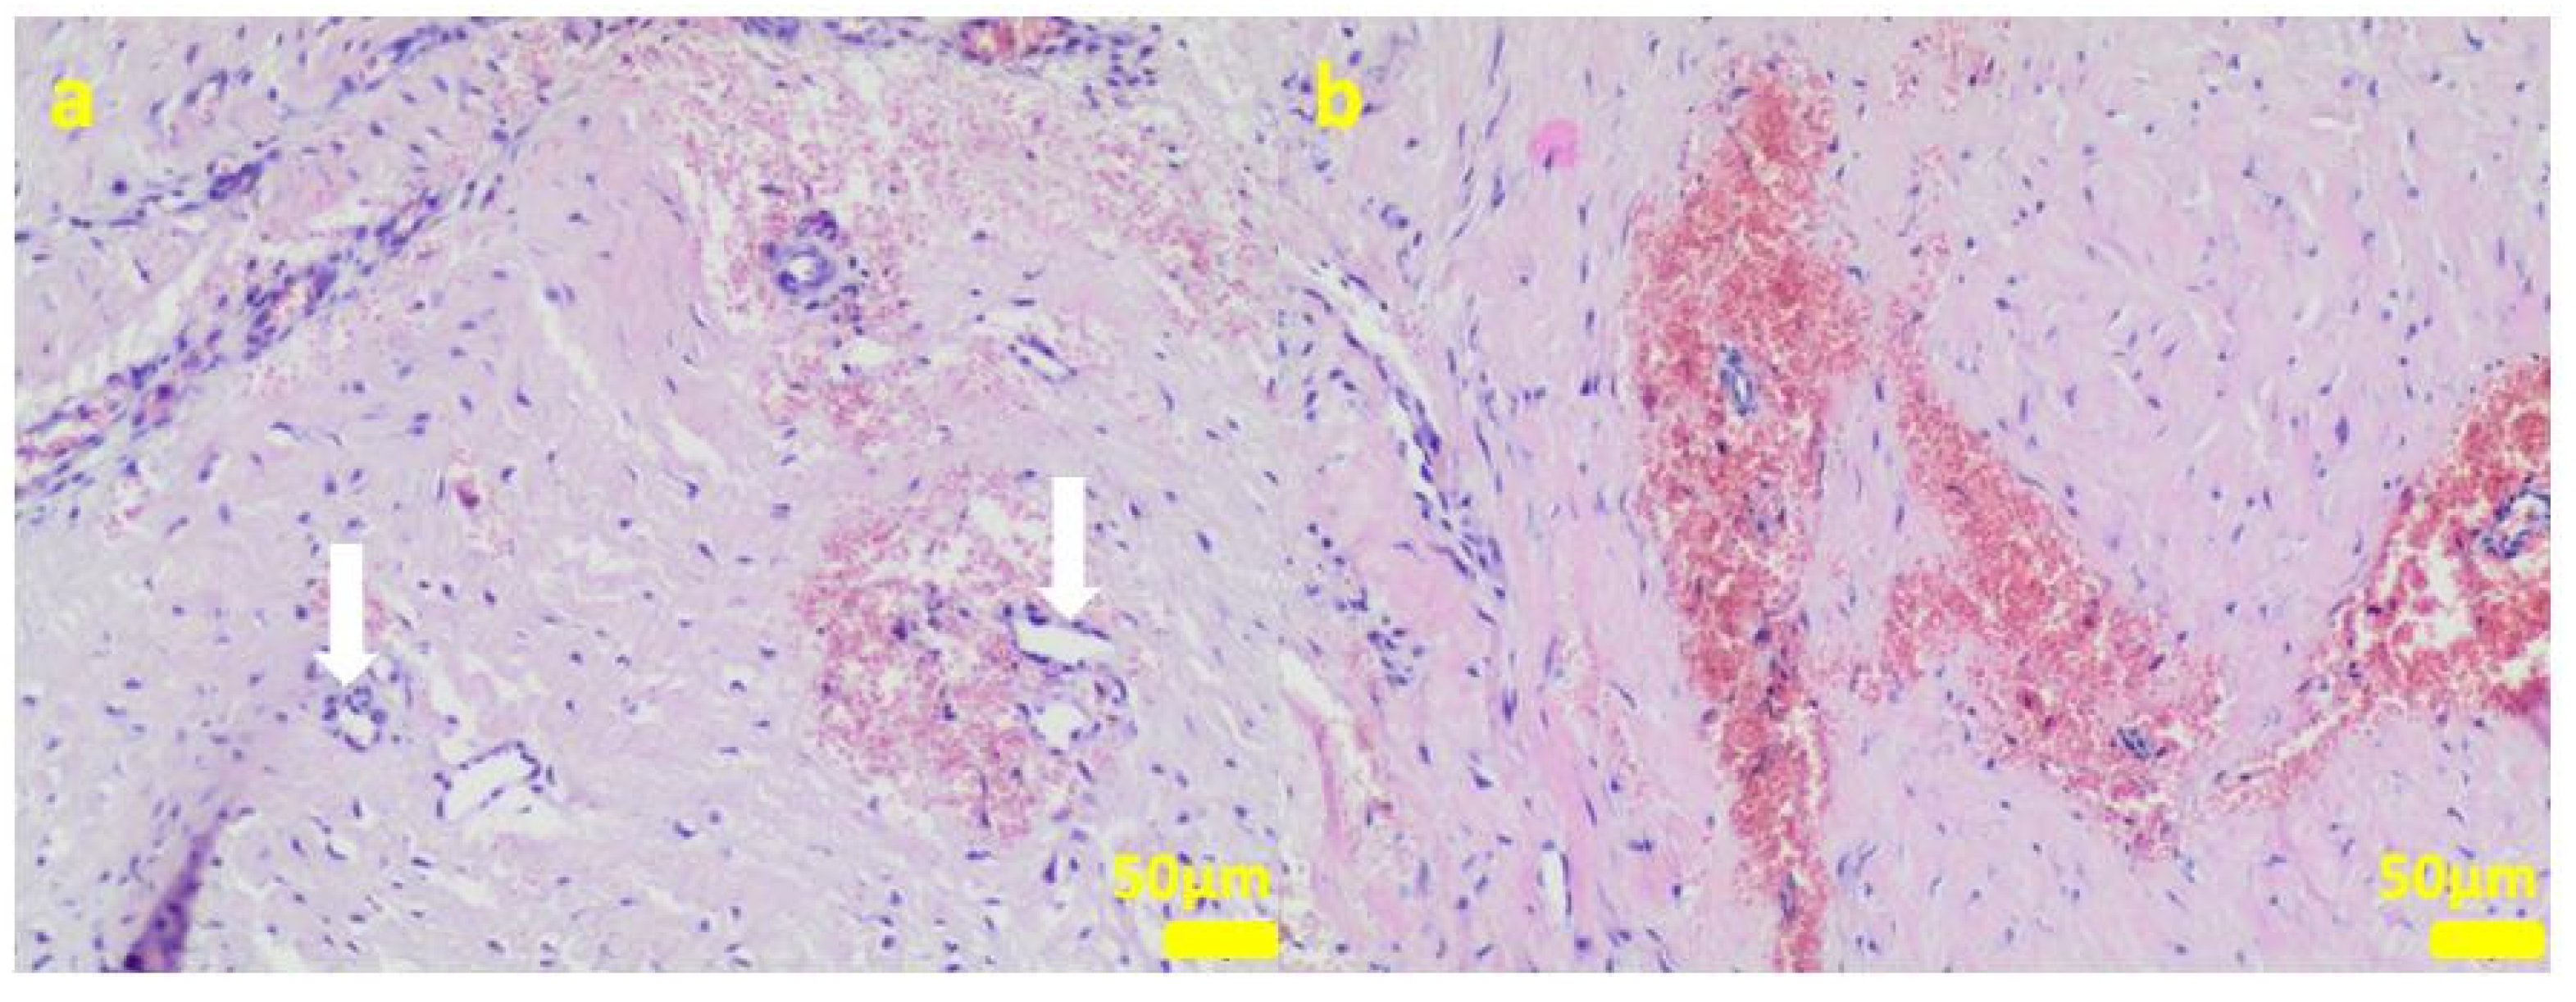

2.1. In Vitro Examinations

2.2. In Vivo Study

4.3. Cell Cultures